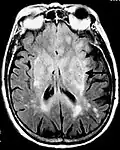

Axial fluid-attenuated inversion recovery MRI image demonstrating tumor-related infiltration involving lenticular nuclei (Arrow). -